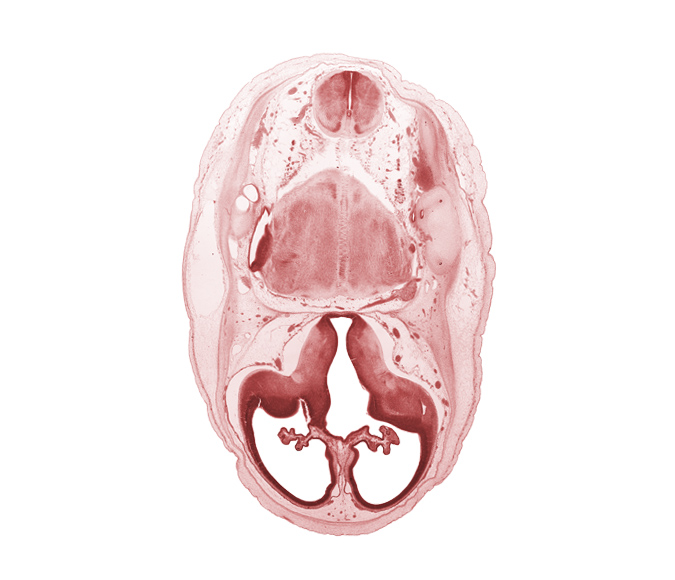

Carnegie Embryo #462 | Location: 5-01-01

Keywords: artifact separation(s), endolymphatic duct, internal carotid artery, lateral ventricle, lateral ventricular eminence (telencephalon), medial accessory olivary nucleus, medial ventricular eminence (diencephalon), myelencephalon (medulla oblongata), posterior communicating artery, pyramidal tract region, root of accessory nerve (CN XI), root of trigeminal nerve (CN V), third ventricle

Source: The Virtual Human Embryo.